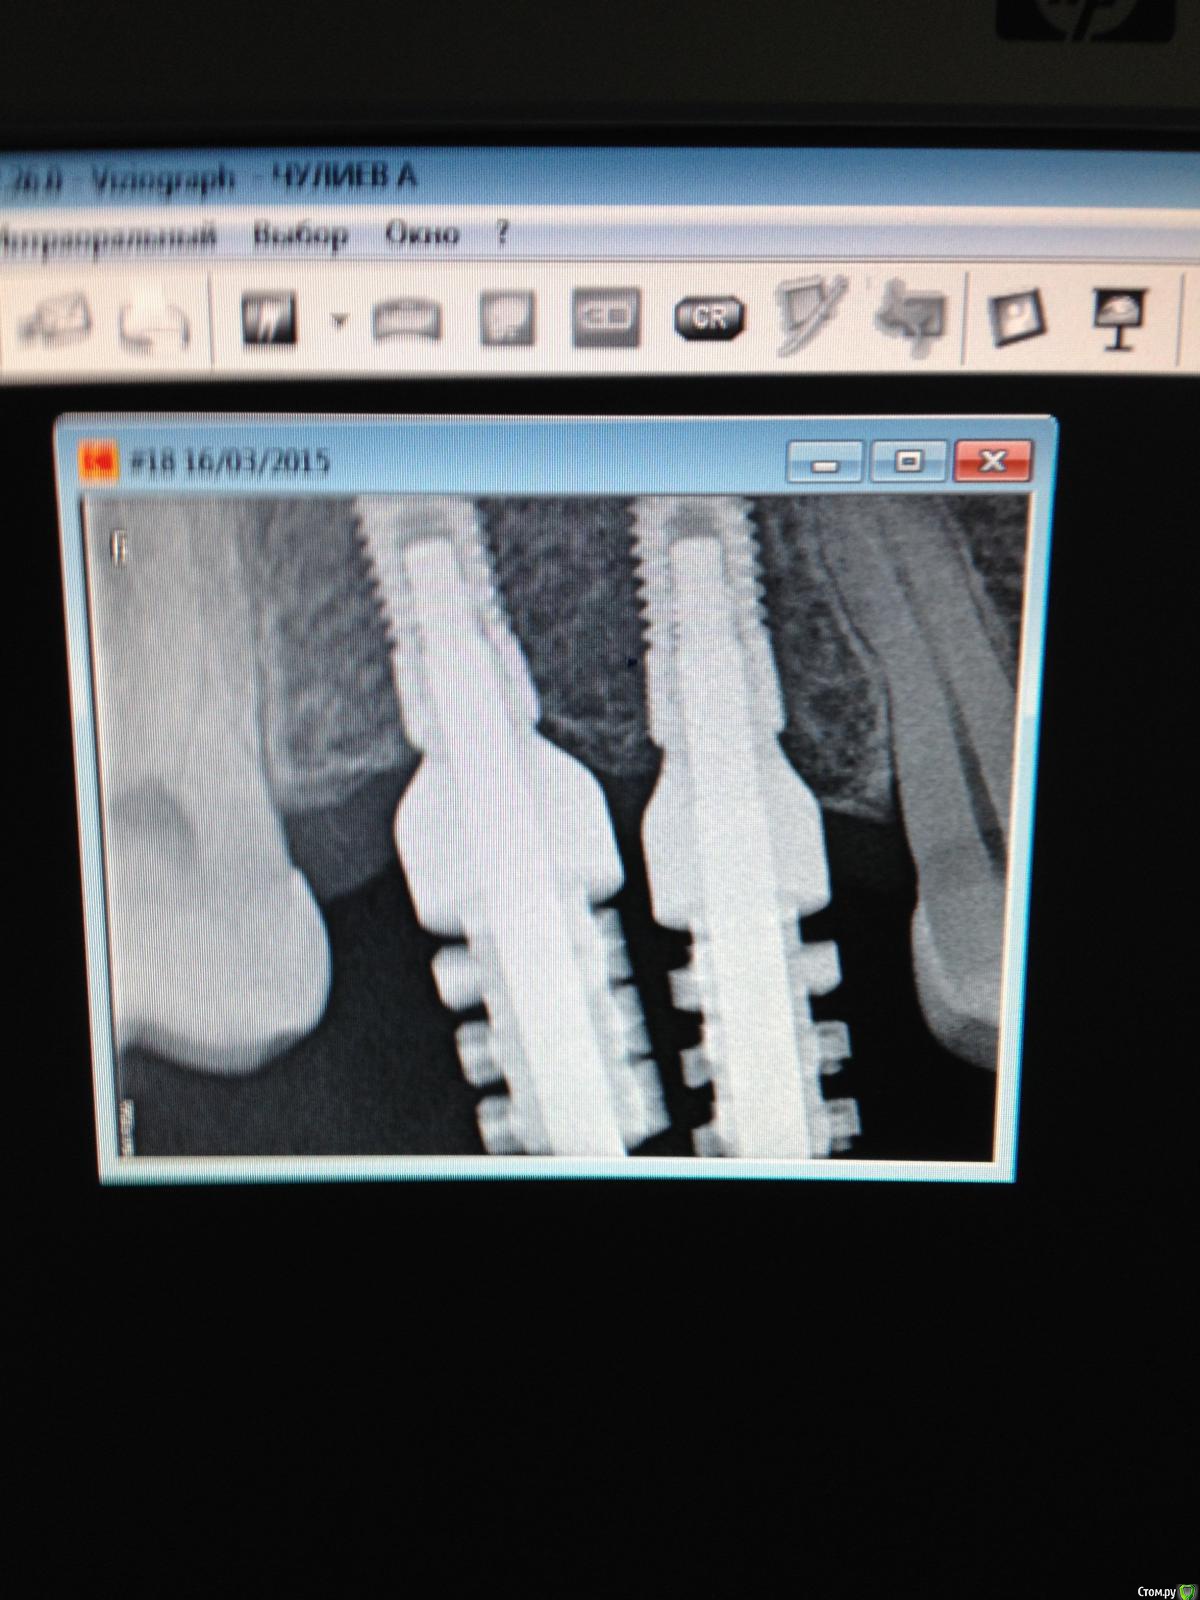

Ильдар Опубликовано 1 апреля, 2015 Поделиться Опубликовано 1 апреля, 2015 Пользователи дентиума , подскажите , пожалуйста.Установлены импланты 3810 и 3812.сняты оттиски.при изготовлении модели , аналог мезиального импланта был использован желтый( 36 ).сейчас дилема. - титановые основания 4,5 на аналоги садятся по-разному.вопрос- повлияет ли использование аналога 36 вместо 38 на конечную работу (объединенные дц коронки на винтовой Fиксации). платfорма ортопедическая на всех дентиумах вроде как идентичная, но ... оттиска уже нет, переделывать ли модель? Ссылка на комментарий

Aquarius Опубликовано 1 апреля, 2015 Поделиться Опубликовано 1 апреля, 2015 Повлияет. Сам попадался несколько раз на этой Дентиумовской особенности)) Градус угла внутр.конуса отличается. Не будет герметизма, хоть и относительного, это раз, и два, во рту картина будет оличаться от модели. Работа не сядет Ссылка на комментарий

kriokov Опубликовано 1 апреля, 2015 Поделиться Опубликовано 1 апреля, 2015 Пользователи дентиума , подскажите , пожалуйста. Установлены импланты 3810 и 3812. нужны белые аналоги под этот диаметр иплантатов. Иначе в посадке проблемы . Ссылка на комментарий

АнтонТЛТ Опубликовано 3 апреля, 2015 Поделиться Опубликовано 3 апреля, 2015 (изменено) Повлияет. Сам попадался несколько раз на этой Дентиумовской особенности)) Градус угла внутр.конуса отличается. Не будет герметизма, хоть и относительного, это раз, и два, во рту картина будет оличаться от модели. Работа не сядетГрадус такой же, глубина шахты имплантата отличается. Сделано для того, чтобы не истончать стенку шахты (профилактика переломов) у тонких имплантатов и чтобы были универсальные протетические элементы (единая платформа) Изменено 3 апреля, 2015 пользователем АнтонТЛТ 1 Ссылка на комментарий

kriokov Опубликовано 28 мая, 2015 Поделиться Опубликовано 28 мая, 2015 у нас техники подбирают аналоги по диаметру трансфера не правильно это получается?На дентиум не правильно-пусть читают мать часть' аналог на дентиум подбирается только по диаметру установленного имплантата. Антон !все правильно обьяснил Ссылка на комментарий